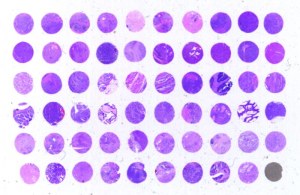

Validation d'anticorps en IHC sur TMA

Cette analyse est réalisée dans des tissus normaux ou cancéreux sur Tissue Micro-Arrays (TMA) inclus en paraffine. => Demande de devis